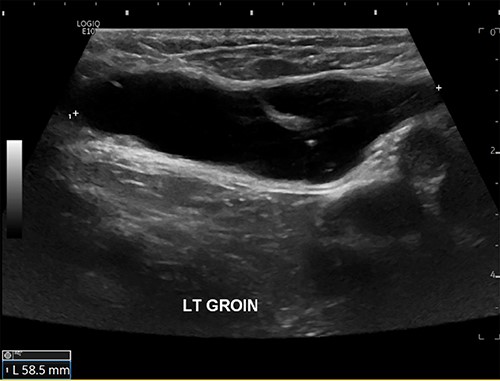

The patient was referred for an ultrasound (US) of the left groin, which showed a contained cyst in the inguinal canal consistent with a CCN (Fig. 1). She was referred to a general surgeon for elective surgical management. A herniorrhaphy was performed with excision of the canal of Nuck and mesh repair. The procedure occurred without complication and the patient was discharged the following day. Histopathology report confirmed a CCN as well as evidence of endometriosis in the adjacent tissue (Fig. 2).

US scan of left groin showing a 59 × 25 × 13 mm anechoic thin-walled cystic structure in the canal of Nuck.

The inconsistent clinical presentation of the more unusual groin mass differentials poses a diagnostic challenge; therefore, ultrasonography is recommended as the first-line imaging modality as it can accurately differentiate between cystic or solid lesions. US appearance typically shows an oval thin-walled cystic lesion with smooth borders and without internal vascularity [5, 9] (Fig. 1). CT and magnetic resonance imaging are more useful alternatives if there are concerns of malignancy; however, US remains a more time- and cost-effective option that is not associated with radiation toward pelvic organs. Ultimately, intra-operative excision of the cyst and histopathology is required to confirm the diagnosis [10].